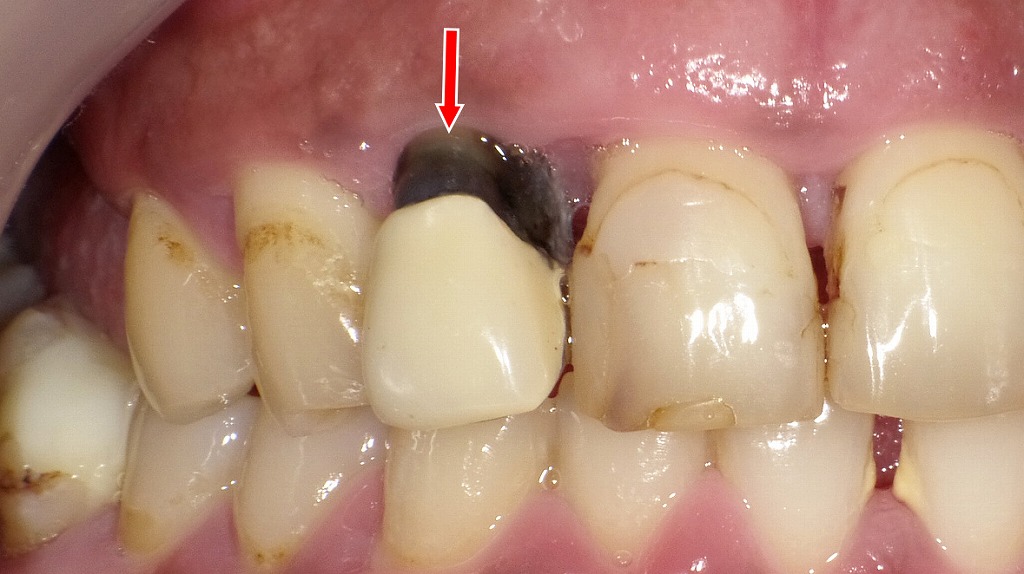

赤い矢印の部分に、上顎2番(前歯)歯肉付近の黒変が確認できます。これは虫歯ではなく、

「保険の硬質レジン前装冠(前歯の差し歯)」の内部にある金属が歯ぐき側に影響して黒く見えている状態です。

● 黒く見える主な原因

- 金属イオンの溶出による歯根・歯肉の黒変・着色

差し歯の内部には、銀合金などの金属で作られた「メタルコア」が入っています。銀合金は長年口腔内で使用されると、金属イオンが溶け出し、

・歯根

・歯ぐき

に沈着して黒く見えることがあります(いわゆる“メタルタトゥー”に近い現象)。